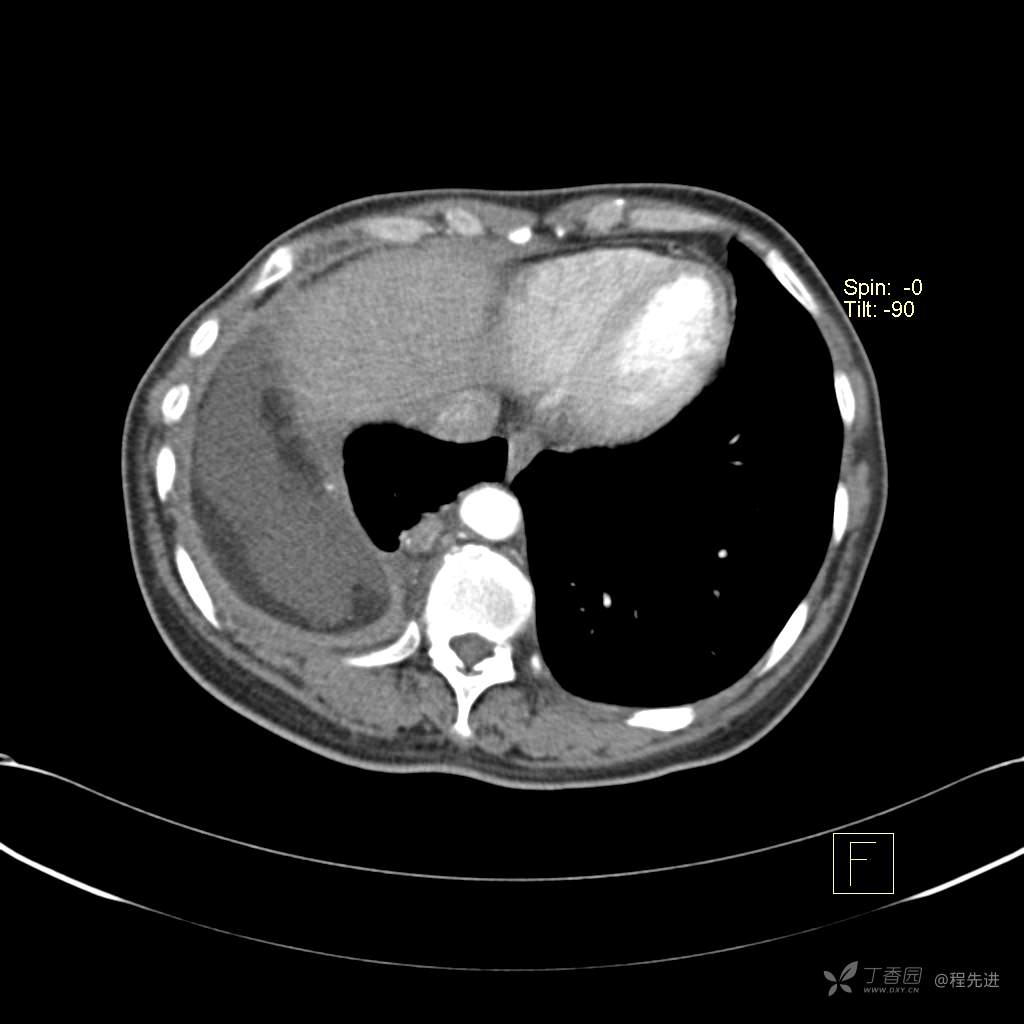

患者性别:女

患者年龄:51岁

简要病史:胸闷半年

肺淋巴管肌瘤病 (7)

乳糜胸 (8)